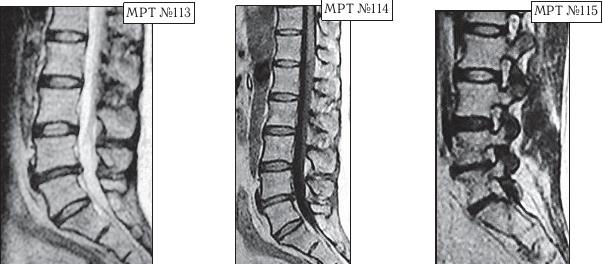

Так вот, сделав МРТ (МРТ №№ 113–115), женщина вернулась со снимками к невропатологу. Он ознакомился с результатами обследования и вместо того чтобы назначить ей консервативные методы лечения при таком диагнозе, направил её… на консультацию к нейрохирургу. Нейрохирург между прочим специалист высокого класса, с большим опытом работы, спасший много человеческих жизней. Однако и он, ознакомившись с результатами обследования, осмотрев пациентку, сделал вывод, что необходима срочная операция по удалению грыжи межпозвонкового диска в сегменте LIV-LV.

На протяжении последних десяти лет у пациентки периодически возникали боли в поясничном отделе позвоночника. Она к ним привыкла и не переживала по этому поводу, так как боли были умеренные, быстро проходили и довольно легко переносились. Но полтора года назад, после физической нагрузки, появились сильные, тянущие боли в ноге. Женщина вынуждена была обратиться в больницу по месту жительства. Пациентку направили к невропатологу, который, осмотрев её, сделал предположение, что возможно у неё «грыжа межпозвонкового диска» и направил женщину на МРТ.

К сожалению, в жизни бывает так, что даже профессиональный специалист иногда вместо пользы может принести серьёзный вред пациенту, исключительно из-за шаблонного подхода. Как ни парадоксально это звучит, но это так. Приведу один пример по этому поводу. Ко мне на приём привели женщину. Привели в буквальном смысле этого слова под руки, при этом она ещё дополнительно опиралась на тросточки. Первое о чём я подумал, когда увидел, с какой осторожностью её ведут и как она переставляет ноги, что у данной пациентки как минимум перелом позвоночника с травмой спинного мозга или как максимум — опухоль в спинномозговом канале. Но в данном случае причина оказалось совсем иной.